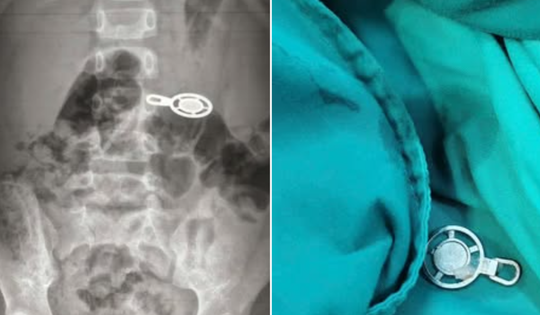

Nuốt móc khóa khi ngủ trưa, bé 4 tuổi phải nhập viện cấp cứu

Từ ca cấp cứu bé trai 4 tuổi nuốt dị vật, bác sĩ cảnh báo nguy cơ tai nạn khó lường khi để trẻ chơi với đồ vật nhỏ.